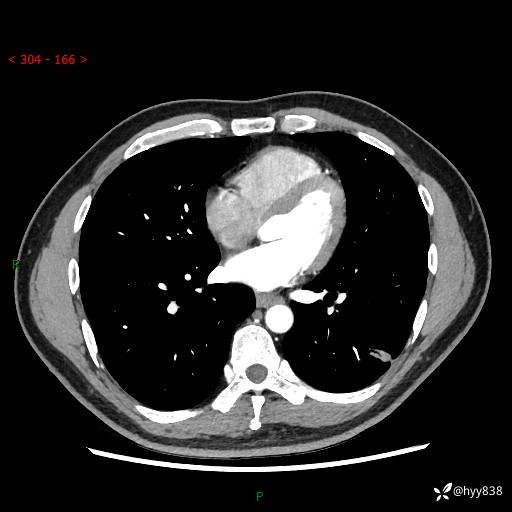

中年男性,胸闷3月余。多发团片、肺小叶分布、空气支气管征、明显强化---结果公布~

现病史:患者3月前出现胸闷,卧位时加重,坐位时缓解,无咽痛、咳嗽,无头痛,无全身酸痛,无结膜充血,无胸痛、心慌,无咯血,无呼吸困难,无咳痰,2024-07-02于当地市第一民医院行胸部CT,结果不详,2024-07-05就诊于我院急诊内科,行胸部CT同时增强,结果示:左肺下叶多发结节灶,考虑感染可能。今患者为求进一步诊治来我院,门诊以“肺部感染”收入我科。 患者本次起病来精神、食欲、睡眠尚可,大小便可,体力,体重无明显变化。

胸部CT平扫+增强

各期CT值:30hu 90hu 77hu